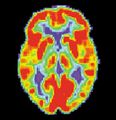

مسح PET لمخ غير مصاب - الصورة مقدمة من مركز الإحالة والتوعية بمرض ألزايمر التابع للمعهد الوطني للشيخوخة بالولايات المتحدة.

مرض ألزايمر هو مرض تنكسي وقاتل يصيب المخ، حيث تُفقد الاتصالات الخلوية بخلايا المخ. يعتبر مرض ألزايمر من أكثر أنواع الخرف شيوعاً.[2] عالمياً، يصاب بمرض ألزايمر حوالي 1-5% من السكان.[3] تقع النساء بشكل غير متناسب ضحايا لمرض ألزايمر، مع وجود أدلة تشير إلى أن النساء المصابات بمرض ألزايمر يظهرن ضعفاً إدراكياً أكثر حدة مقارنة بالذكور المصابين بالمرض، بالإضافة إلى معدل أسرع من التدهور السلوكي.[4]